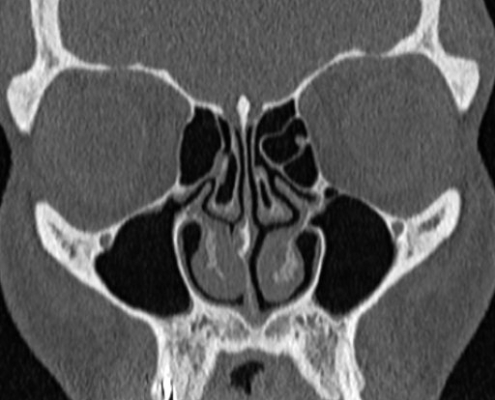

Le Scanner étudie le cerveau, la cage thoracique, l’abdomen ou encore les os. Il recherche des anomalies qui ne sont pas visibles sur des radiographies standard ou à l’échographie.

Le Scanner appelé aussi tomodensitométrie est un examen qui utilise les rayons X.

Son principe consiste à réaliser des images en coupes fines de votre corps. Au lieu d’être fixe, le tube de rayons X va tourner autour de vous et grâce à un système informatique puissant, des images sont obtenues. Ensuite, elles sont imprimées sur un film pour être étudiées. Dans la plupart des cas, un produit de contraste à base d’iode est utilisé pour améliorer leur qualité. Il peut être injecté par voie intraveineuse, avalé ou encore introduit par l’anus.

Cet examen présente l’avantage de donner des informations très précises sur les organes étudiés. De l’extérieur du corps, on peut le découper en tranches ou le reconstruire en trois dimensions